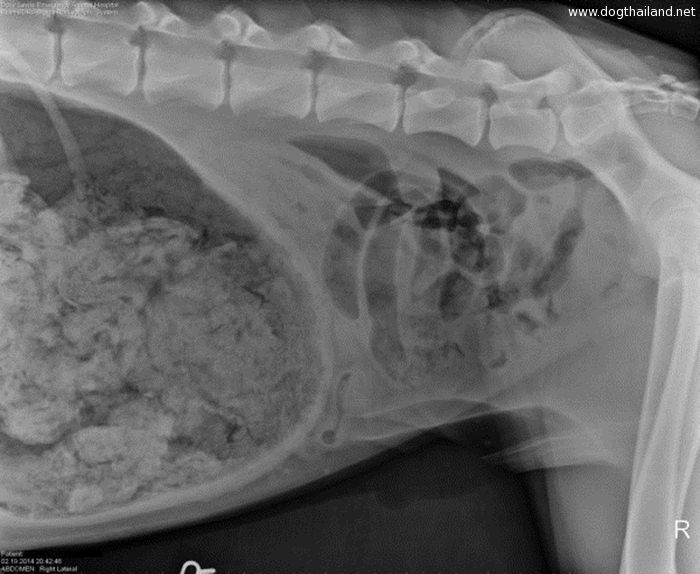

โดยทางเว็บไซต์ทเวนตี้มินูทเท็น ของสวิตเซอร์แลนด์ ได้เผยแพร่ภาพเอ็กซเรย์ภายในท้องของสัตว์เลี้ยงหลากหลายชนิดด้วยกัน ซึ่งแต่ละภาพนั้นชวนให้สยดสยองเป็นอย่างมากเลยทีเดียว

เพราะเมื่อแพทย์เห็นฟิล์มเอ็กซเรย์ก็ถึงกับผงะ และช็อคไปเลยทีเดียว จนต้องรับทำการล้างกระเพาะอาหารให้กับสัตว์เลี้ยงเหล่านี้อย่างเร่งด่วนทันที เเนื่องจากในกระเพาะของสัตว์เลี้ยงเหล่านี้เต็มไปด้วยสิ่งแปลกปลอมมากมาย ที่ไม่น่าเชื่อว่า "จะกินได้...?" นั่นเอง จะมีอะไรบ้าง ไปดูกันเลย

4. ภาพเอกซเรย์ภายในท้องของสุนัขตัวหนึ่งที่กลืน "แท่งกระดูกยาว 30 เซนติเมตร"